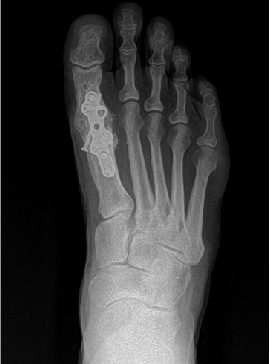

Therefore, most surgeons use common radiographic signs to rule out primary delay and eventual non-union. Some of these signs include the presence of a bridging callus, three of four cortices being bridged by callus formation and the resorption of fracture lines.2 Evaluation of the hardware across the proposed fusion site is also a good indicator. Hardware failure often indicates motion across the site with a lack of bony union, which places more force on the hardware, resulting in failure. Radiographic assessment is limited to the rate at which bony changes are visible in radiographs, which can take months.

Conversely, surgeons should also attend to the factors they can control. Ensure a stable rigid construct; augmentation of osteogenic, osteoinductive or osteoconductive properties; and establishment and maintenance of a normal anatomic alignment when possible. With the development of more anatomic contouring for internal and more “user-friendly” external devices, there are a variety of options available to choose from when determining how to obtain stable and rigid alignment. A combination of both plates and screws is often indicated to prevent any micromotion across the fusion site.